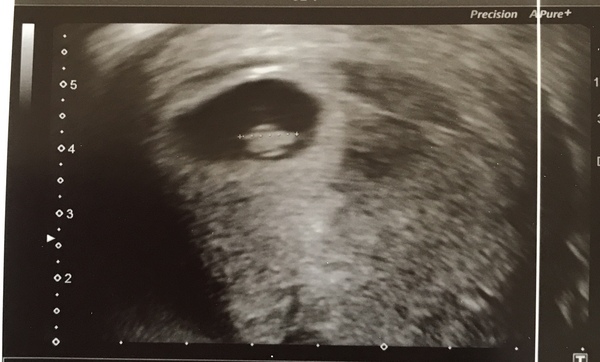

Scan went well! All looking perfect 🥰. Will post pic later - I swear it looks like a roast chicken! Xxx

@Chooklass congratulations on your little roast chicken 😂 I think mine looked like a little chicken too

Soooooo glad all is perfect in there @Chooklass 😍 Of course yours was always going to look like a roast chicken! 🐔🍗😂 I think mine had more than a passing resemblance to a seahorse 🤔🌊 🐴 😁

I didn’t need a full bladder by the way! Nurse said only for abdominal scans 🤷‍♀️! Was so relieved as I was bursting 😂

Measuring 7 or 7+2 depending on angle. They found it difficult to get a good pic but we saw heart beating - amazing! EDD 15th Oct 🥳. The staff seemed so happy for us, it was really lovely.

We were told there’s a 95% chance of success now that we’ve seen heartbeat at 7 weeks. I remember crying on the day of my 3dt because the stats said 15% chance of success for us then. We feel incredibly lucky! 🥰

@Chooklass how lovely is that 🥰 amazing congratulations again! What a lovely roast chicken 🐥so you calling yours chicken then 🐣or chick? ❤️

I agree, I can see a chicken!!

Wow congratulations 🥳 🤩@Chooklass this gorgeous and it's measuring perfect. I think we both had same due date.... did yours changed after today's scan or you initially calculated 15th Oct ?